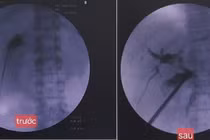

ong-mat.jpg

Hình ảnh ống mật đã được làm sạch sỏi sau phẫu thuật trên bệnh nhân N.T.L 45 tuổi - Ảnh BVCC